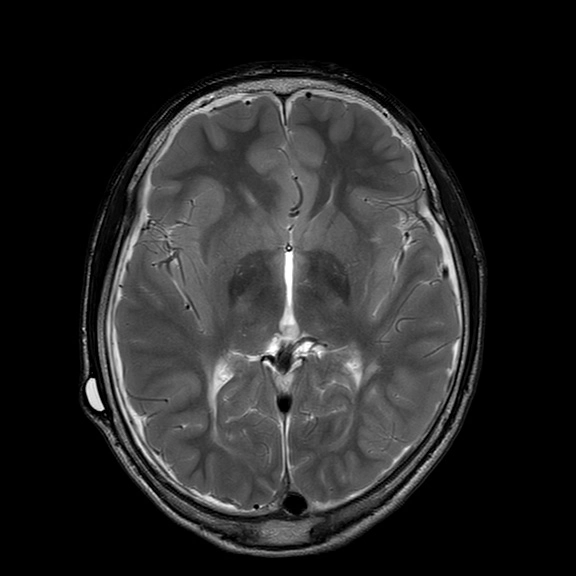

Não úng thủy áp lực bình thường (NPH - Normal-Pressure Hydrocephalus)

• Não úng thủy áp lực bình thường (NPH - Normal-Pressure Hydrocephalus)